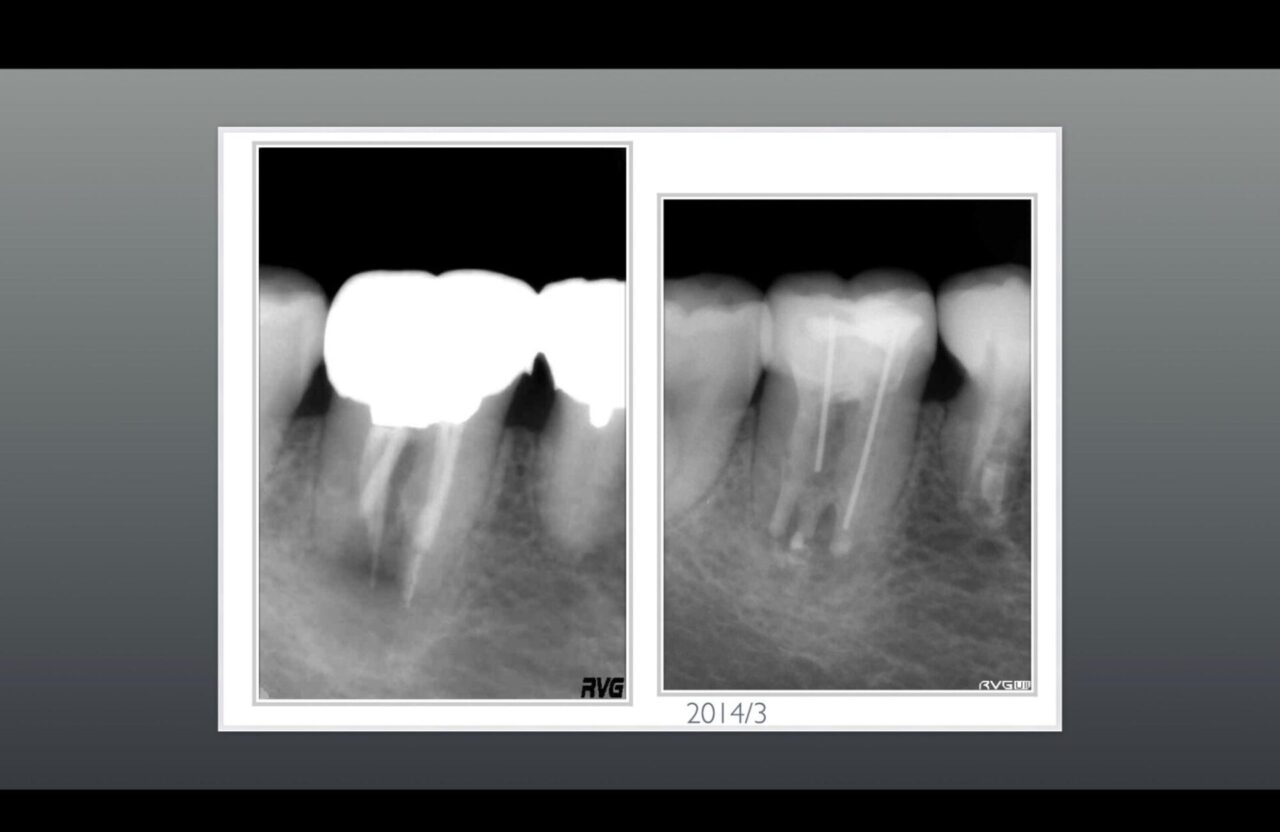

術前のレントゲンと術後のレントゲン写真➁

術前に根尖部の骨吸収画像及び破折ファイルが2本以上確認する事ができる。

術後のレントゲン写真では、根尖部の骨は再生され根管内にあった異物はきちんと除去されている。